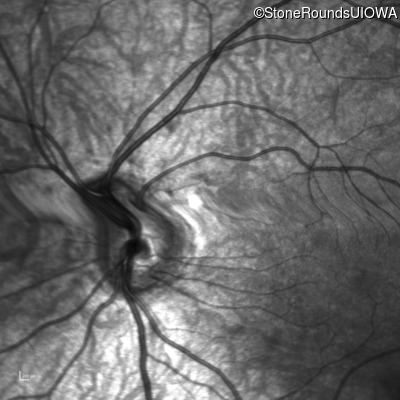

Infrared Fundus Photograph - Right - 10/160 +1 sc

Exemplar

Infrared Fundus Photograph - Left - 10/200 sc